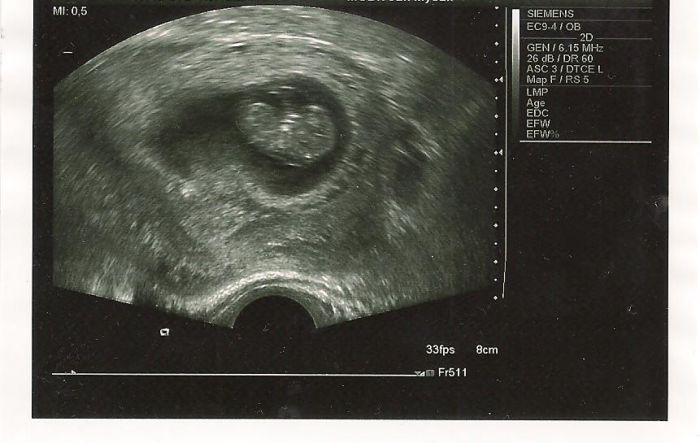

Ahoj holky, tak už jsem po kontrole, vše je v pořádku, miminku krásné bije srdíčko. Podle utz je velké 2,5 cm a vychází o den míň 9+2. Příští úterý jdu na krev ohledně screaningu a dostanu průkazku :-). A taky mám fotečku tak jí sem dávám :-)